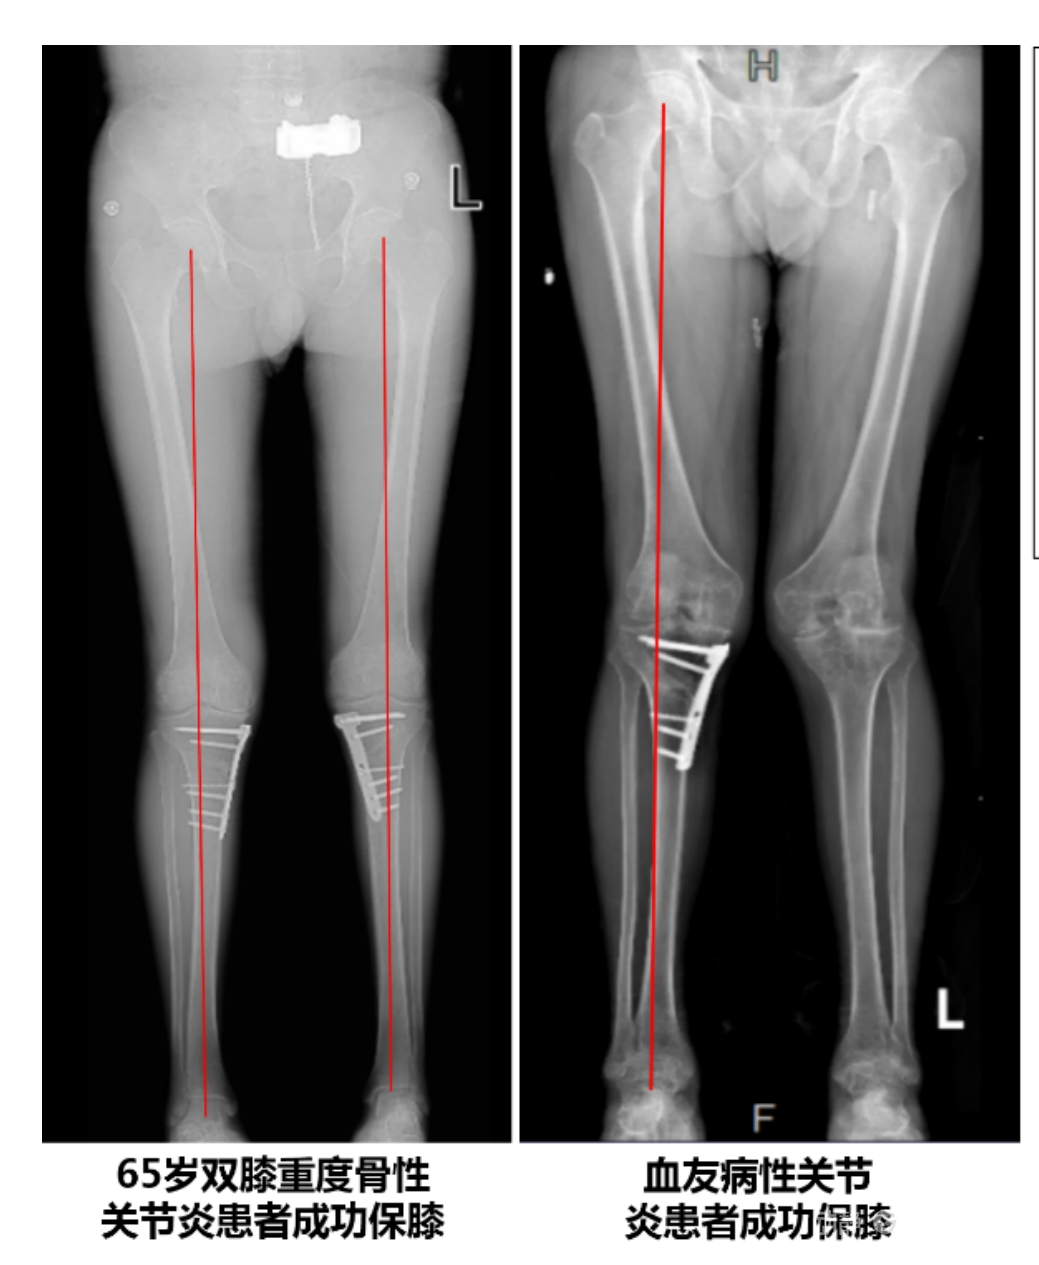

4.2 APTT-HTO脛骨高位截骨術

2025年7月,貴州醫科大學附屬醫院骨科團隊原創研發的腘肌前結節中脛骨高位截骨保膝術(Anterior Popliteus Transtibial Tuberosity-High Tibial Osteotomy, APTT-HTO)及其提出的脛骨結節分區與腘肌保護理論,登上了國際頂尖學術舞臺。該成果在全球最具影響力的專業會議之一——日本骨科協會第98屆年會上進行了兩次學術發言。[8]

該手術具有經皮微創、保留原生膝關節結構、符合階梯治療原則等優勢,通過調整下肢力線可促進部分軟骨再生,術后關節功能接近正常(如下蹲、爬山),患者還能從事中重體力勞動。相比其他術式,其有效規避了髕骨低位、血管損傷、合頁骨折等潛在并發癥。

目前,APTT-HTO技術已成功應用于千余名患者,幫助保留自身膝關節。此類保膝手術適用于單間室膝關節炎患者(如 “羅圈腿”),核心是通過調整力線糾正畸形,減輕磨損間室壓力、發揮健康間室作用,延長膝關節壽命。若出現膝關節疼痛、保守治療無效且X線顯示關節間隙部分狹窄,建議及時就醫評估是否適合手術。

APTT-HTO脛骨高位截骨術